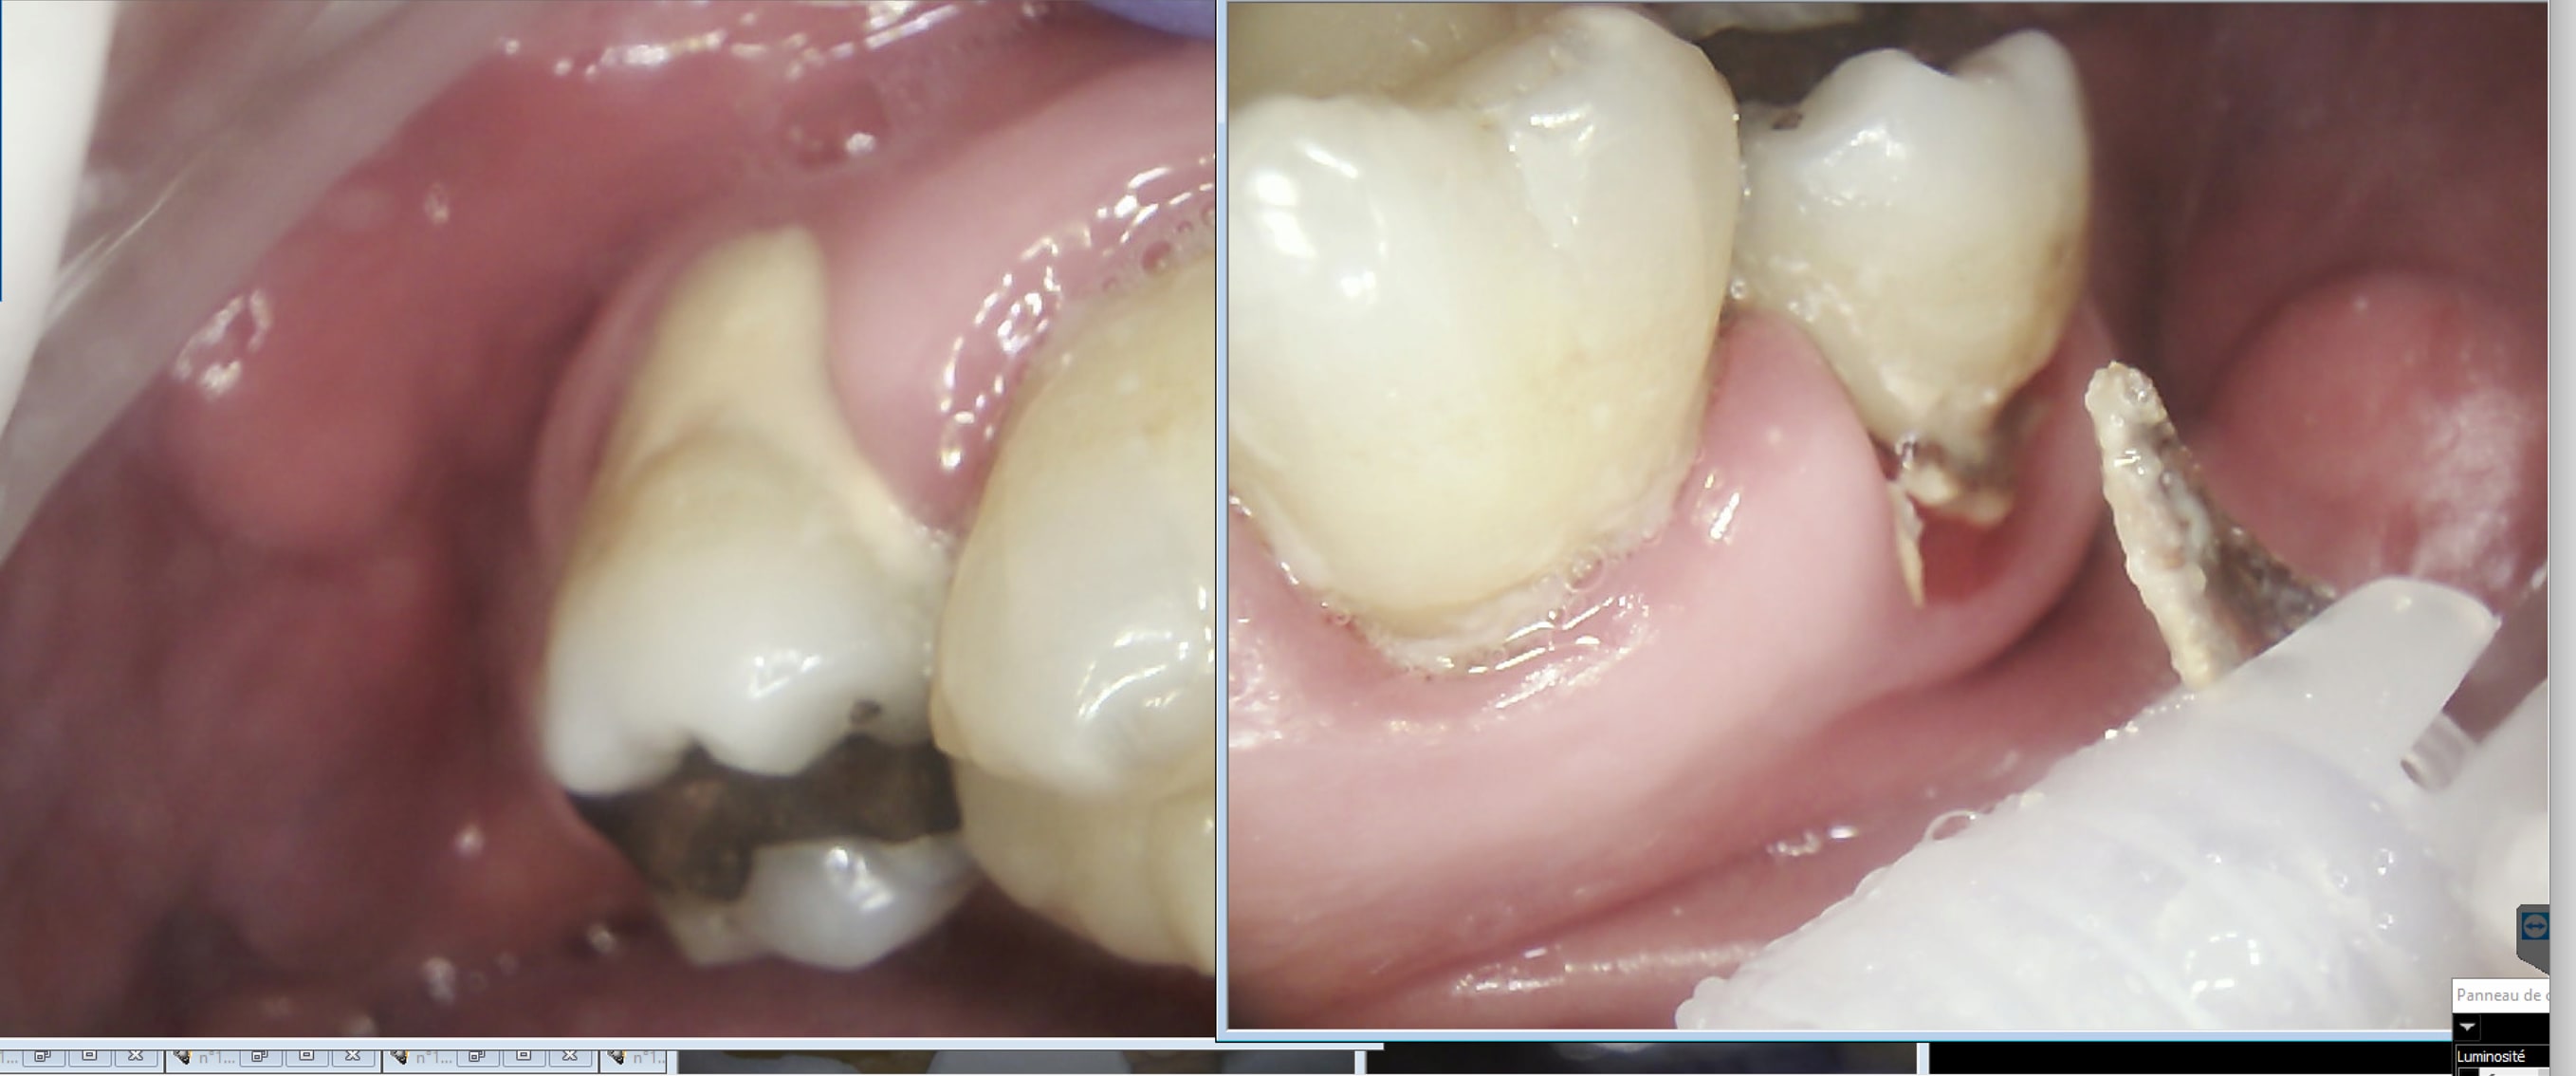

Vous avez tous eu un prothésiste vous disant que si la prothèse ne descend pas c'est à cause de l'empreinte ( tirage par ex) . Que répond t'il quand vous dupliquez l'empreinte que vous l'envoyez à un second et que la prothèse descend ? Hein ? En bas à droite inlay core prothésiste 1 sur modèle prothésiste 2.

Ah oui en vestibulaire c'est pas moi qui ait défoncé la gencive. Endo because grosses sensibilités après détrartrage. -)))